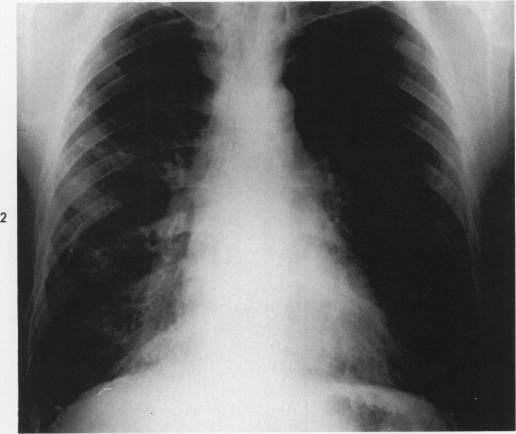

Desquamative interstitial pneumonia. An electron microscopic study.

Am J Pathol. 1970 Sep;60(3):347-70.